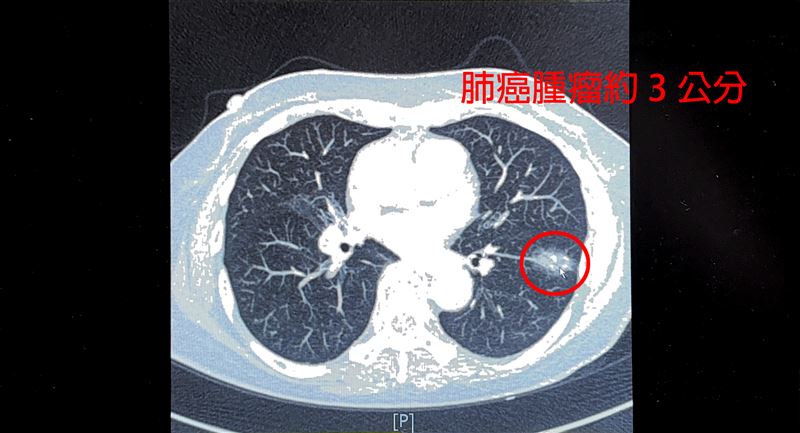

女患者左下肺葉有一顆接近3公分的惡性腫瘤。(圖/中國醫藥大學新竹附設醫院提供)

一位75歲女性患者,不菸不酒,今年安排健檢LDCT肺癌篩檢,發現左下肺葉有一顆接近3公分的惡性腫瘤,求診中國醫藥大學新竹附設醫院,溝通後執行達文西手術。由於患者曾在10多年前罹患肺結核,因此肺部淋巴像石頭一樣硬,甚至出現與血管沾黏的情形,經過約4個小時手術,病患住院3天後出院,恢復狀況良好,目前持續追蹤。

中國醫藥大學新竹附設醫院胸腔外科醫師謝義山表示,在執行達文西肺葉切除手術,發現病患因為肺結核感染的病史,造成縱膈淋巴結跟石頭一樣硬,與血管沾黏嚴重,一旦手術時分破血管,瞬間可能就是數千甚至上萬cc的大流血。幸好透過達文西手術,在機器手臂輔助下進行血管分離結紮,左下肺葉有3條主要肺動脈分離後,雖然兩條分支分破流血,但順利止住流血,最後只有200cc的出血量。開完刀建議要努力深呼吸、咳痰,盡早下床活動,休息2周即可以從事輕便的工作,建議2至3個月後再從事粗重工作或是運動。